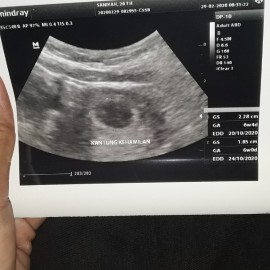

usg hri ini alhamdulillah udh memasuki 6 minggu???

Anak pertama deg deg gan??❤